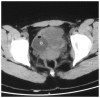

Extragastrointestinal stromal tumors (EGISTs) are mesenchymal tumors occurring outside the gastrointestinal tract, with histological, immunohistochemical and molecular genetic characteristics similar to those of gastrointestinal stromal tumors (GISTs). The immunohistochemical examination usually demonstrates a positive expression for CD117. GISTs are rare neoplasms and EGISTs are even less common. This is the report of a case of EGIST in the urinary bladder of a 15-year-old adolescent female patient who presented with painless gross hematuria. Pelvic computed tomography revealed an irregular soft tissue density mass, sized 5.7×4.8 cm, in the bladder. Partial cystectomy was performed in April, 2011. There was no recurrence during follow-up over the next 35 months, as determined by transabdoninal ultrasonography and cystoscopic examination. The patient in this study did not receive any molecular-targeted drugs. To the best of our knowledge, this is the first reported case of an EGIST of the urinary bladder in an adolescent patient.